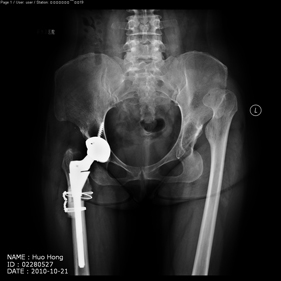

Department of Adult Joint Reconstructive Surgery

shortening osteotomy and total hip replacement for bilateral severe dysplasia of hip with high riding